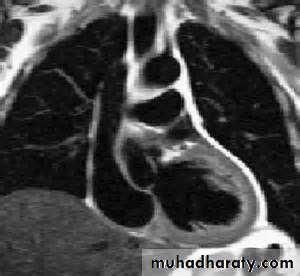

Endoscope -like ultrasound probe which is passed into the oesophagus under light sedation and positioned behind the LA. This produces high-resolution images.Computed Tomographic Imaging :

Useful for imaging the cardiac chambers, great vessels , pericardium, and mediastinal structures and masses

And recently even the coronaries (CT coronary angiography).

Magnetic resonance imaging

Magnetic resonance imaging (MRI) requires no ionising radiation and can be used to generate cross-sectional images of the heart, lungs and mediastinal structuresCardiac catheterization